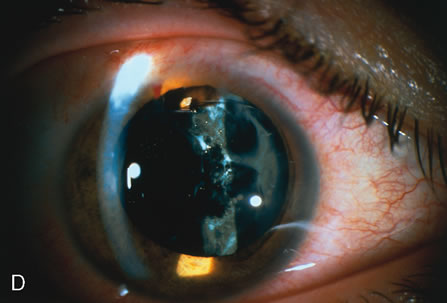

When phacoemulsification became available, it was quickly applied to the removal of children's cataracts because it provided the surgeon with better control of the flow of irrigating solutions and provided improved control of the aspiration flow and pressure.4 The instrument also added a new capability, that of being able to mechanically disrupt the lens nucleus and cortex to facilitate aspiration of the lens. Although the phacoemulsification instrument was helpful for removing lens cortex, it was ineffective in cutting or removing the posterior lens capsule. At the conclusion of the phacoemulsification procedure, the posterior capsule was left intact. When capsular opacification occurred, it was treated with a discission procedure, an operation that consisted of making a cut in the posterior capsule with a bent needle, a Ziegler knife, or a modification of the latter (Fig. 1). If the membrane was thick and resisted opening with a knife, an intraocular scissors was necessary to open the lens capsule.

The advantage of leaving the posterior capsule of the lens intact after cataract surgery is that it retains a barrier between the anterior chamber and vitreous. This prevents the vitreous from entering the anterior chamber, and it theoretically preserves the ocular anatomic relationships after cataract surgery. The disadvantage of leaving the posterior lens capsule intact is that when the capsule opacifies, a second procedure is needed to re-establish a clear visual axis. To achieve this, a second anesthetic is administered and an incision is made into the clear cornea. The chamber is deepened with a viscoelastic material and a knife or other instruments are introduced into the anterior chamber to cut or tear the posterior capsule so that the visual axis can be cleared (Fig. 1).

When the vitreous suction-cutting devices became available, they were quickly employed to remove cataracts in children. In addition to providing control of aspiration pressure and control of the flow of irrigation solutions, they also added the ability to remove some or all of the posterior lens capsule, even when the capsule had a thick fibrovascular stalk associated with persistent hyperplastic primary vitreous (PHPV) or a thick capsular plaque (Fig. 2). These fine-tip suction-cutting instruments provided sufficient control of the anterior chamber depth, thus permitting the surgeon to precisely open the posterior capsule and, if necessary, safely remove vitreous from the anterior chamber. Keech and co-workers,12 in a contemporaneous surgical series, showed that having the ability to remove the posterior lens capsule and perform an anterior vitrectomy reduced the need for secondary procedures from 75%, if the capsule was left intact, to 11% after capsulectomy and anterior vitrectomy. They found that when a large section of the posterior lens capsule was removed, it provided a lasting optical opening and reduced the requirement for additional surgery.